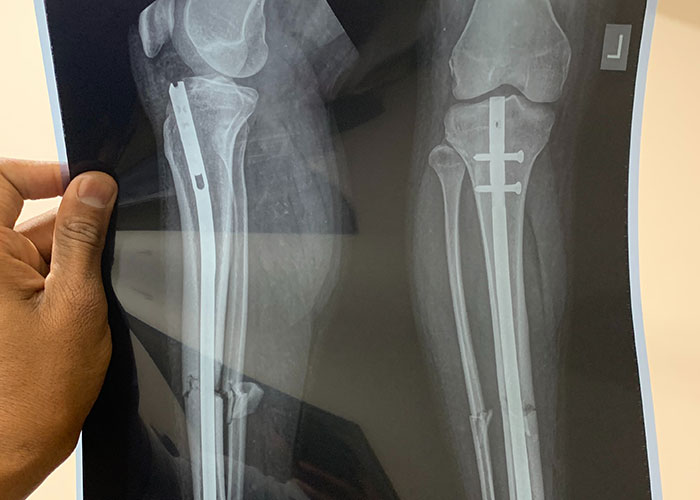

Un hombre de unos 50 años acudió a trauma para que le cosieran el muslo izquierdo. No es una herida poco común en una zona agrícola. Al hablar con él mientras le cosían, me dice que se cayó de una escalera mientras cortaba una rama y que el machete le cortó al caer. Le dije que le iba a hacer una radiografía de toda la pierna solo por si acaso. Siguió diciendo que estaba bien, que le dolía un poco la rodilla pero lógicamente eso era por la caída, estuve de acuerdo, pero le pedí que fuera al departamento de rayos X solo por si acaso.

A regañadientes fue y volvió. Los rayos X mostraron una fractura helicoidal en casi toda la longitud de su fémur. Además de ser una fractura peligrosa, se supone que el fémur es el hueso más doloroso de romper y él estaba caminando.

Al final hubo que enseñarle la fractura para que se sentara en una silla de ruedas y se pusiera en manos de los traumatólogos. La tolerancia al dolor de ese hombre todavía me impresiona.